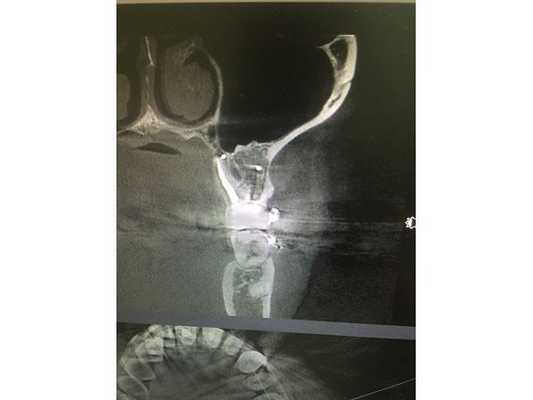

По данным компьютерной томограммы, в зубе три канала, тень пломбировочного материала определяется на всём протяжении каналов в виде непрерывной линейной структуры, рентгенологически верхушки корней зуба обтурированы, т. е. закрыты.

Обнаружен дополнительный канал со стороны щеки, содержимое канала не просматривается. В области нёбного канала видна тень металлической плотности, по конфигурации она соответствует анкерному штифту.

В области верхушек корней визуально определяется деструкция (разрушение) кости без чётких контуров. Плотность участка разрушения снижена, характерный костный рисунок частично сохранён. Область разрушения частично затрагивает альвеолярную бухту гайморовой пазухи. Кортикальная пластинка, отделяющая гайморову пазуху от зубов, в проекции деструкции прослеживается фрагментарно.

- Каналы обработали и запломбировали. На контрольном рентгеновском снимке видно, что корневые каналы запломбированы на всём протяжении.

Через два года после лечения сделали контрольную компьютерную томографию. Кость вокруг корня зуба полностью восстановилась. Обострений, боли и дискомфорта после лечения пациент не отмечал.